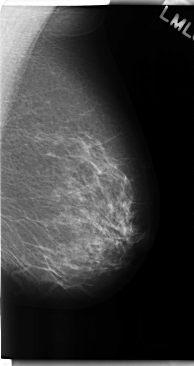

C_0182_1.LEFT_MLO

LEFT_MLO LINES 4752 PIXELS_PER_LINE 2512 BITS_PER_PIXEL 12 RESOLUTION 50 NON_OVERLAY